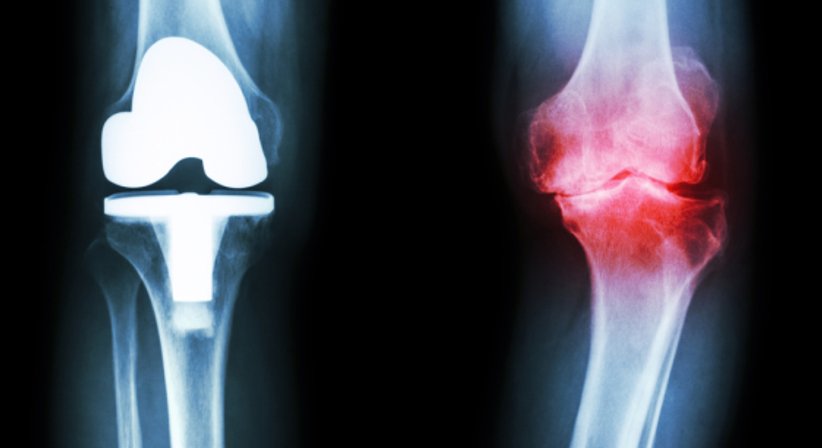

Arthrose/Knieprothese

Arthrose ist die häufigste Ursache für Gelenkschmerzen und betrifft mehr als die Hälfte aller über 50-Jährigen. Da Arthrose nicht heilbar ist, kann der Knorpelabbau durch eine Behandlung auch nicht wieder rückgängig gemacht werden.

Eine Knieprothese wird dann nötig, wenn das Knie aufgrund fortgeschrittener Arthrose zunehmend an Funktionalität und Beweglichkeit verliert und sich die Schmerzen mithilfe konservativer Therapien bzw. einer minimal-invasiven Operation (Arthroskopie) nicht mehr ausreichend mildern lassen.

Für die Operation stehen unterschiedliche Knieprothesen sowie unterschiedliche Vorgehensweisen zur Wahl.

Welche Knieprothese/Vorgehensweise im jeweiligen Fall am besten geeignet ist, orientiert sich an der individuellen Anatomie des Patienten, am Schweregrad der Arthrose und an anderen Faktoren.